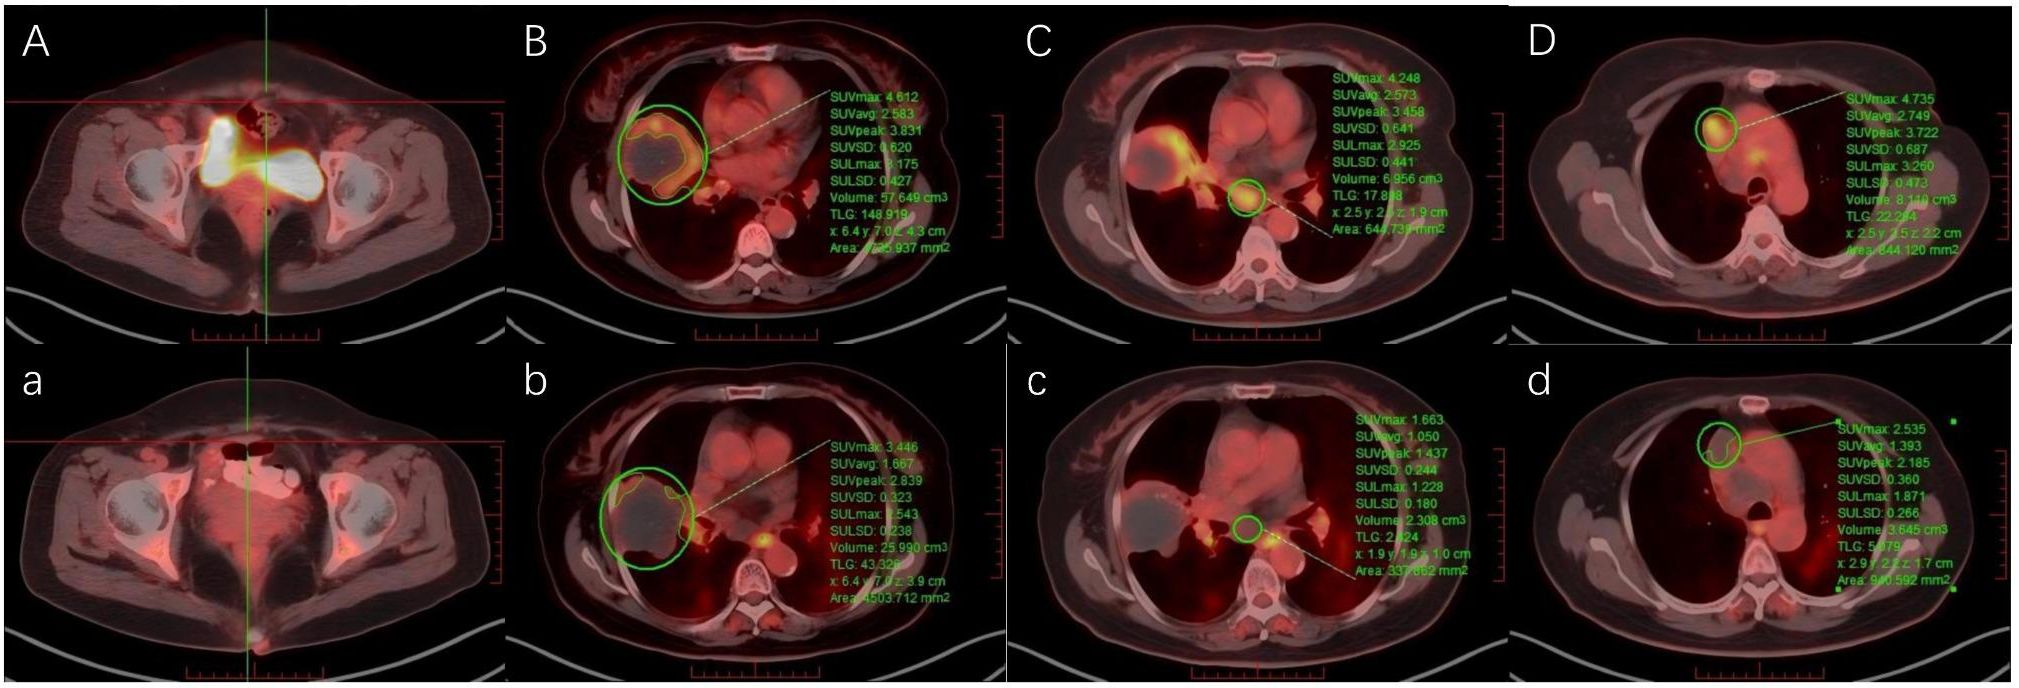

Urachal carcinoma is a rare and aggressive malignancy with limited treatment options, particularly in the metastatic setting. Standardized therapeutic protocols are lacking. This case report describes a 62-year-old female patient who developed pulmonary and mediastinal lymph node metastases more than four years after surgical resection of urachal carcinoma. For this case, a combined regimen of Spatially Fractionated Radiotherapy (SFRT), CapeOX (capecitabine plus oxaliplatin) chemotherapy, and bevacizumab targeted therapy was developed. The treatment course was complicated by grade 4 hematologic toxicity and radiation-induced esophagitis, both of which were successfully managed. To our knowledge, this represents the first documented application of SFRT in urachal carcinoma. Although significant tumor shrinkage was not observed, the patient achieved symptomatic relief, metabolic remission, and stable disease during follow-up.